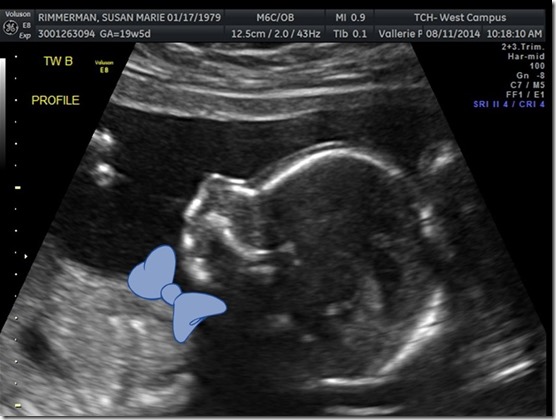

Was your guess correct! August 16, 2014 By srimmerman We are super excited to share what baby Rimm A and baby Rimm B are! Both boys are happy and healthy! Baby RImm A is 12oz and Baby Rimm B is 11oz. They are both VERY active and I’m sure going to be giving us a run for our money once they are born!! Share this: Share on X (Opens in new window) X Share on Facebook (Opens in new window) Facebook Like Loading... Related